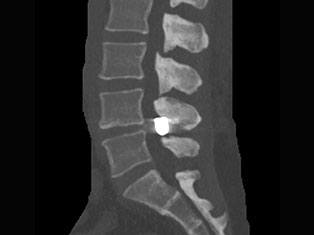

Degenerative Spine

The phrase "degenerative changes" in the spine refers to osteoarthritis of the spine. Osteoarthritis is the most common form of arthritis. Doctors may also refer to it as degenerative arthritis or degenerative joint disease.